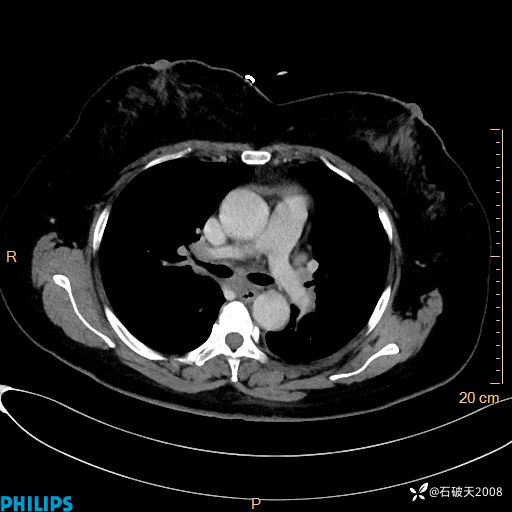

肺结节病?纵膈型肺癌?淋巴瘤?有点意思,欢迎围观

女 52岁 主 诉:咳嗽10余天,咳痰2天。

动脉期